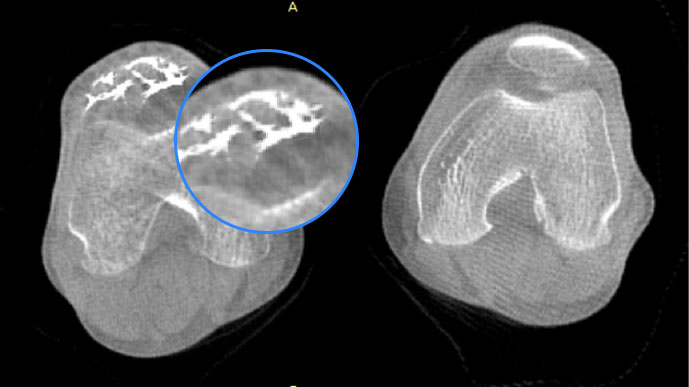

膝关节

FOV 250mm

FOV 350mm